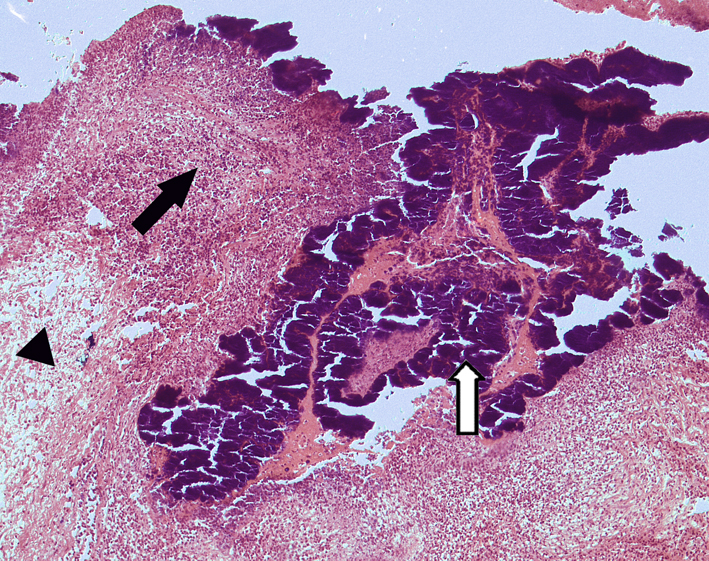

5.Hepatocellular carcinoma